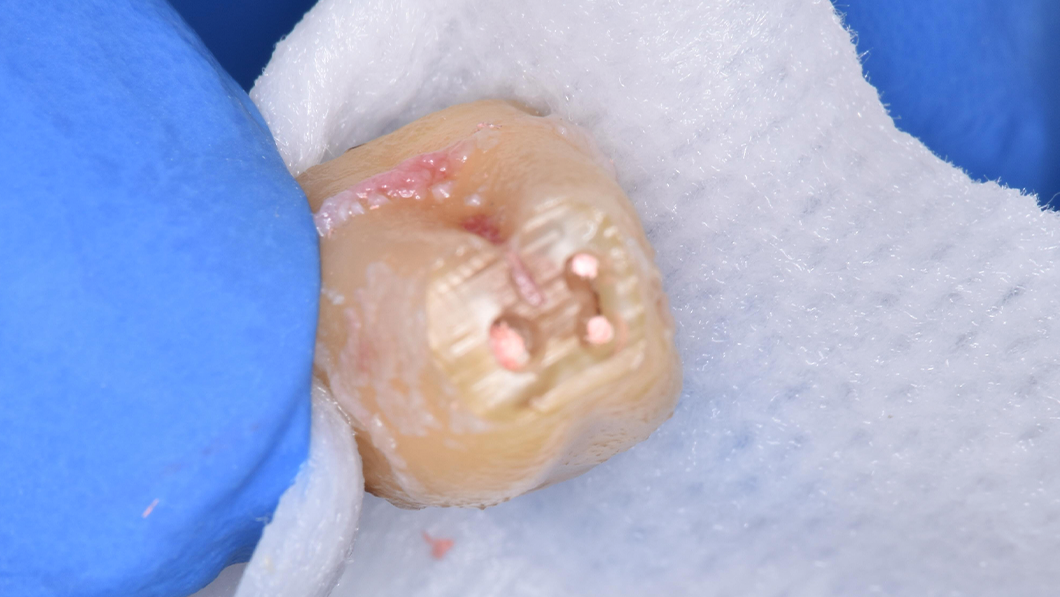

意図的再植

治療内容 補綴物除去後歯牙を一度抜歯。口腔外で根切および根管形成を行い逆根管充填後口腔内へ戻し固定。

動揺落ち着いたのを確認後CAD/CAM冠にて補綴

治療に伴うリスク 術中:抜歯時に歯根破折の可能性

術後:歯根吸収(置換性吸収)、付着の部分的非獲得(部分的な深いポケットの形成)